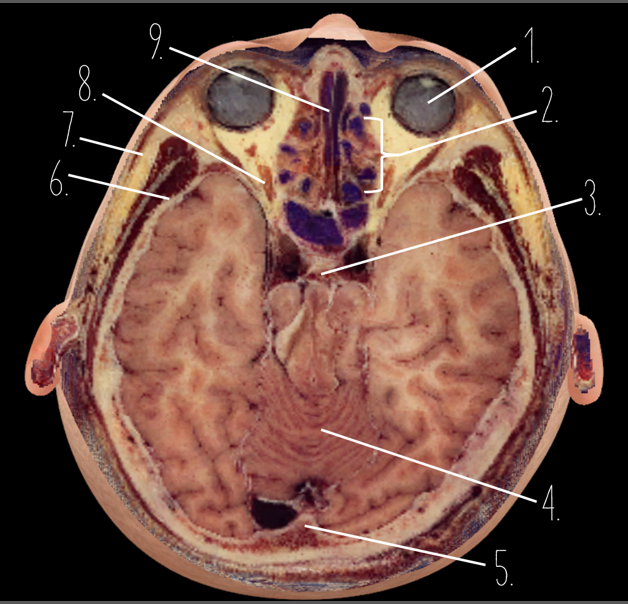

1?

Nasal Bone

2?

Maxillary Sinus

3?

External Acoustic Meatus

4?

Pons

5?

Cerebellum

6?

Mastoid Air Cells

7?

Mandibular Condyles

8?

Sphenoid Bone

9?

Maxillary Bone